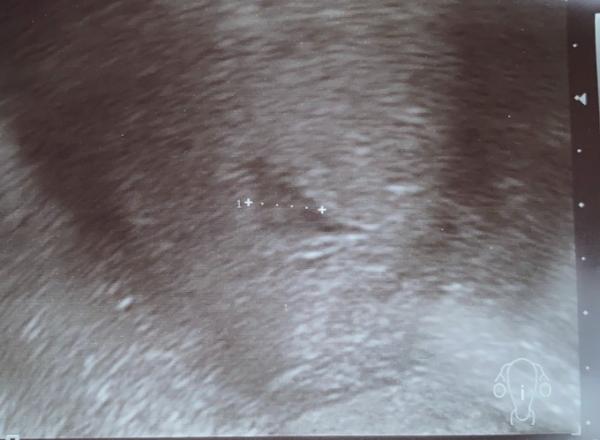

Alles optimal! Das Zwergilein hat sich perfekt eingenistet! Man konnte heute nur die Fruchthöhle sehen und ich bin heute 5+3, ET wäre dann der 29.7 Nächster Termin am 17.12, dann hoffentlich mit Herzschlag und Embryo Das Bild von heute hänge ich mal an, auch wenn man eigentlich nichts sieht ! Ich freue mich

Bild zu Heute FA Termin gehabt - Forum für Juli - Mamis